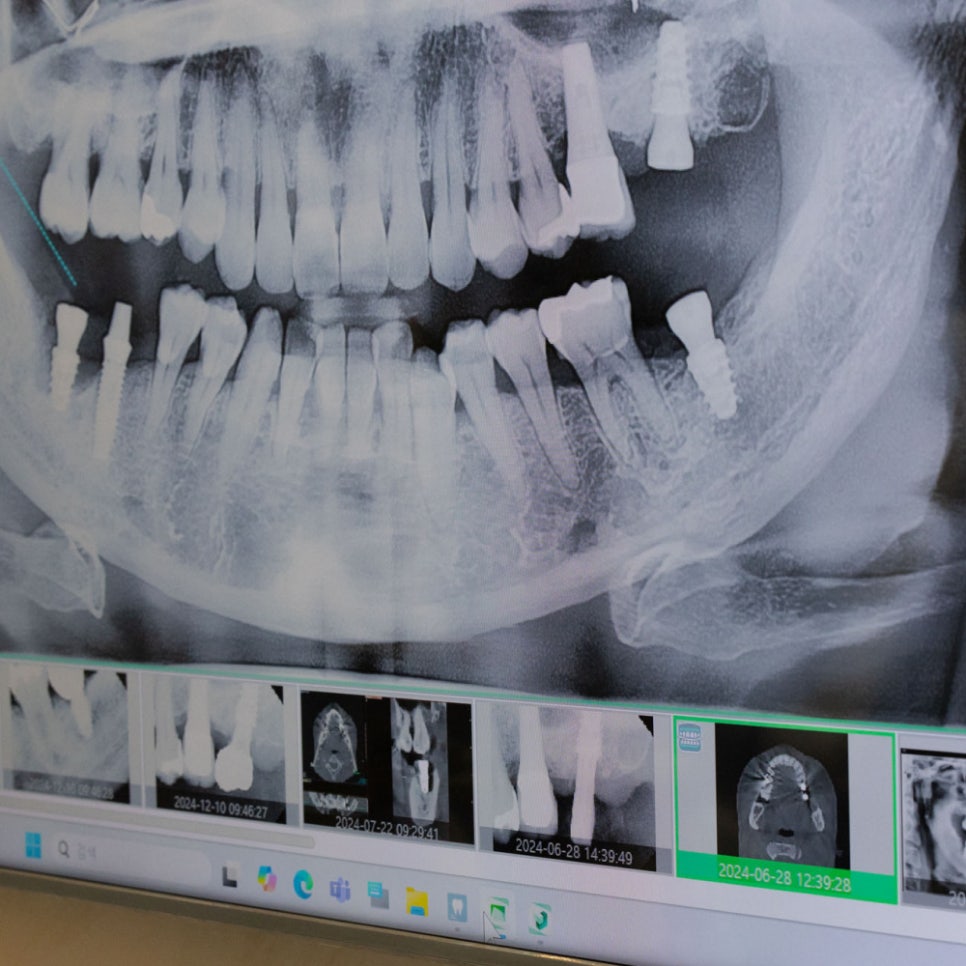

회복기간을 단축하는 하루플란트의 플라즈마 임플란트 시스템

플라즈마 임플란트란, 임플란트에 플라즈마 기술을 적용해

탄화수소를 제거하고 표면을 활성화시키는 솔루션입니다.

탄화수소는 임플란트 표면의 친수성을 떨어뜨려서,

혈액의 응집을 방해하고 골유착력을 감소시키는데요.

플라즈마 기술이 적용된 임플란트는 표면의 탄화수소가

제거됐기 때문에 혈액의 응집과 골유착력이 향상되게 되죠.

이는 결과적으로 임플란트 회복기간이 크게 향상되게 됩니다.

✔ 재생력이 향상되어, 회복기간 단축됩니다.

✔ 잇몸뼈 결합이 원활해져, 초기 안정성이 증가합니다.